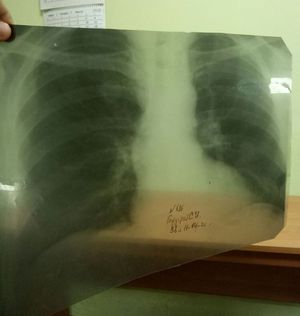

What's your diagnosis??

Boot shaped heart tetralogy of fallot overriding of aorta is clearly visible

TOF?